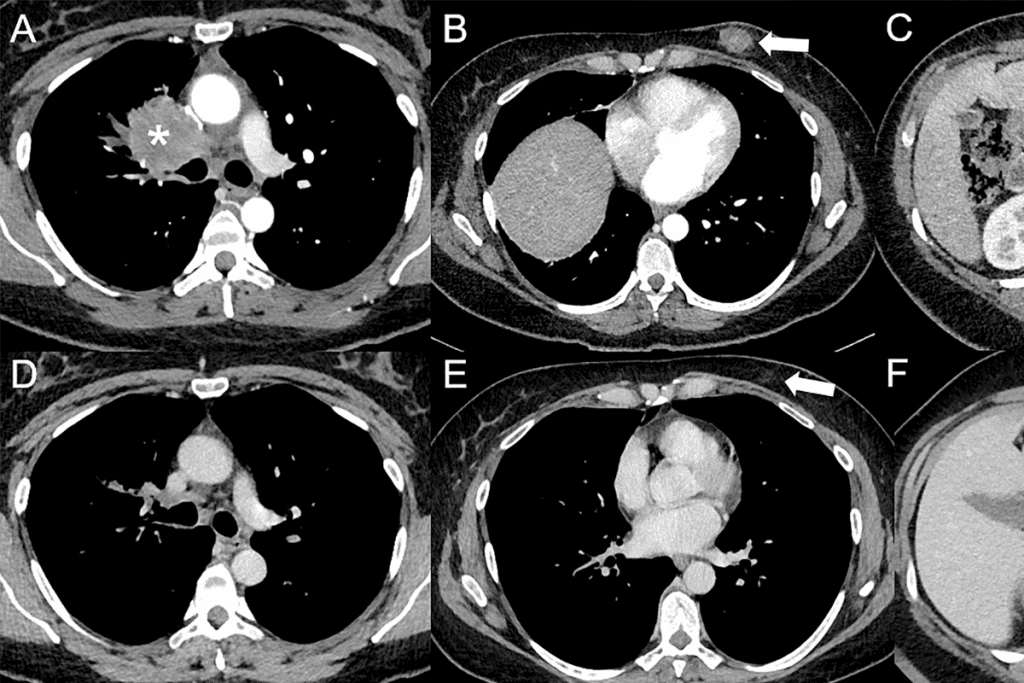

CT Scan Accuracy Cancer: Detection of Metastatic Disease

CT scans are key in finding metastatic disease, mainly in lung cancer patients. They give vital info for planning treatments and staging.

Sensitivity and Specificity Rates

CT scans’ accuracy is shown by their sensitivity and specificity rates. Sensitivity is how well they spot those with metastatic disease. Specificity is how well they miss those without it. The rates vary based on the organ and metastasis size.

Size Limitations in Metastasis Detection

CT scans struggle to find small metastases. Smaller lesions, under 5 mm, are hard to spot. New CT tech, like thinner slices, helps but size is key.

Accuracy Variations by Organ Site

CT scans’ accuracy changes with the organ. Finding liver or adrenal gland metastases is harder than in lungs or lymph nodes. Location and nearby structures impact reading. Knowing these differences is vital for accurate treatment plans.

In summary, CT scans are essential for finding metastatic disease. But, their accuracy depends on several things like sensitivity, size, and organ site. Improving imaging tech is key to better detection.

CT scans are very important in staging lung cancer. They help see the tumor size, lymph nodes, and if cancer has spread. Being able to spot metastasis early is key for knowing the stage and future.